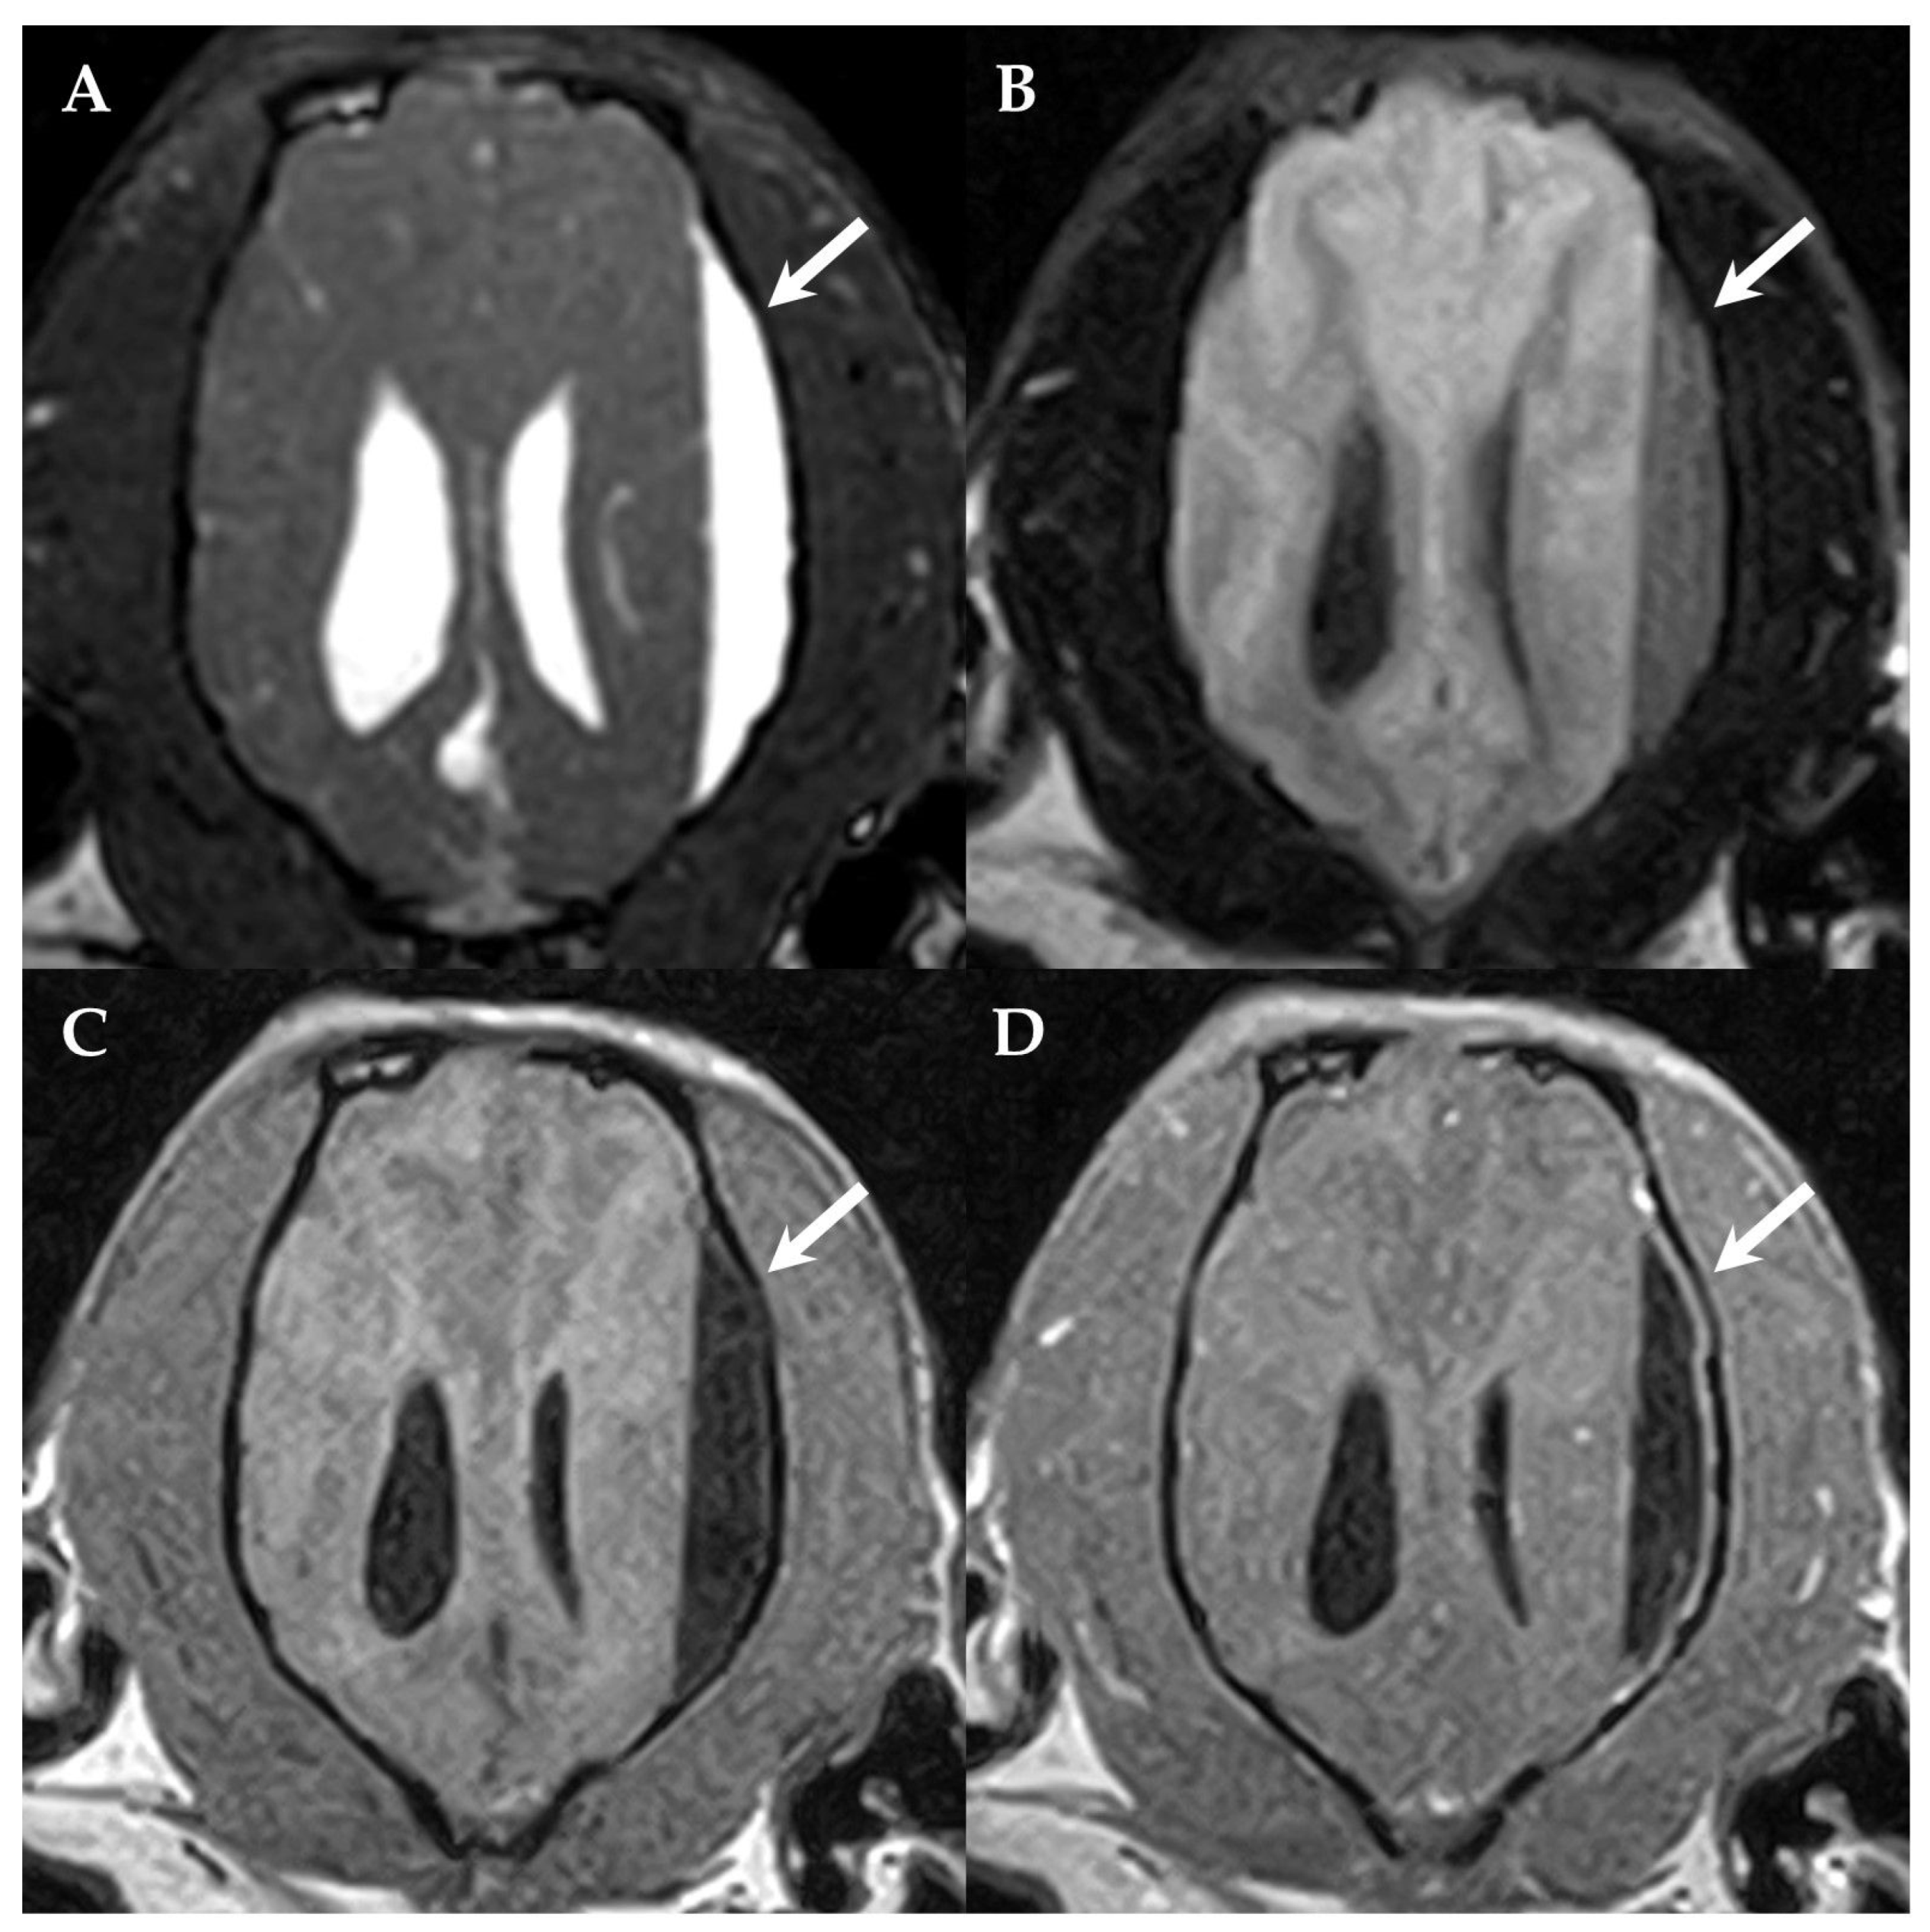

Figure 1.

First MRI of the dog’s brain. Dorsal BASG (A), FLAIR (B) 3DT1W (C) and 3DT1W after contrast administration (D) showing the subdural fluid accumulation (SFA, arrows) compressing the left parietotemporal lobe and the left lateral ventricle. The SFA is BASG hyperintense (A), incompletely compressing on FLAIR (B), 3DT1W hypointense and demonstrates a mild contrast-enhancement of the adjacent dura mater (D). The left side of the patient is on the right side of the image.